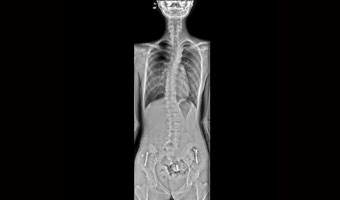

Klinik Vakalar

Tam klinik uygulama, her yerde bakım

Ortopedik yaralanmalar

Tek çekimde tam omurga ve alt ekstremite görüntüleme.

Ergen skolyozu ve geleneksel göğüs röntgeni taraması.

Uygulama Görüntüleri

Tıbbi tarama